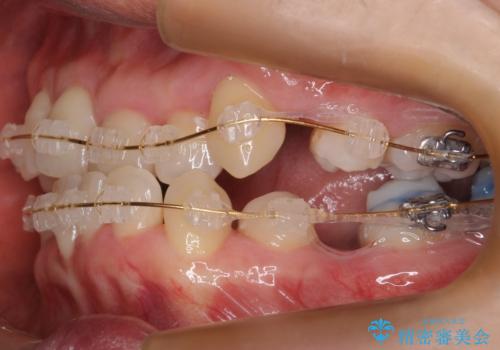

- 矯正装置

- 審美装置

- 受け口を主訴に来院。

下あごが大きく、顎の手術を含めた矯正をおすすめしましたが、手術は怖いので絶対にしたくないとのことでした。

歯並びのみを治す矯正は難しく、長期にわたる治療になるとご説明しました。

かみしめもあり、骨も固く、歯根も長いためなかなか歯が動かず、患者様も治療する側も忍耐を要する長期戦となりました。